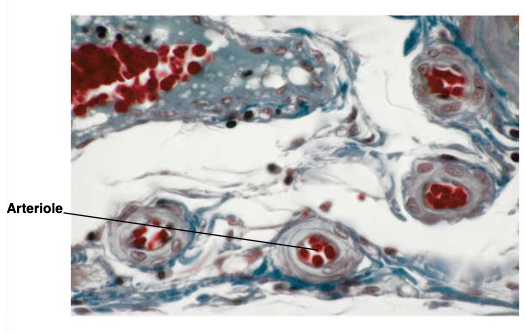

3 wall layers of arteries or veins

tunica intima, media, and externa

muscle layer between intima and media

internal elastic lamina

muscle layer between media and externa

external elastic lamina